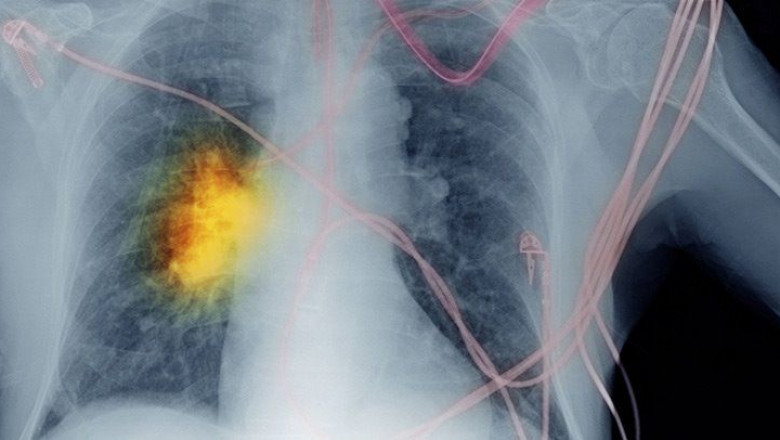

Europe non-small cell lung cancer diagnostics market is expected to reach USD 846.60 million by 2028 from USD 331.31 million in 2020, growing at a steady CAGR of 12.5% in the forecast period of 2021 to 2028.